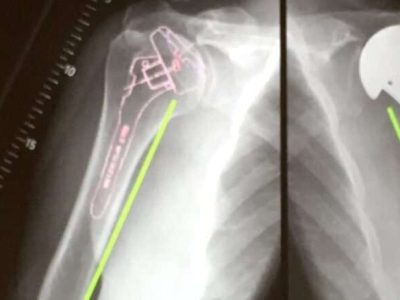

Normal Shoulder In the normal shoulder (glenohumeral joint), motion occurs across smooth surfaces lined with cartilage. As seen on the X-ray to the right, the normal shoulder has smooth surfaces lined with cartilage that cushions the impact between…